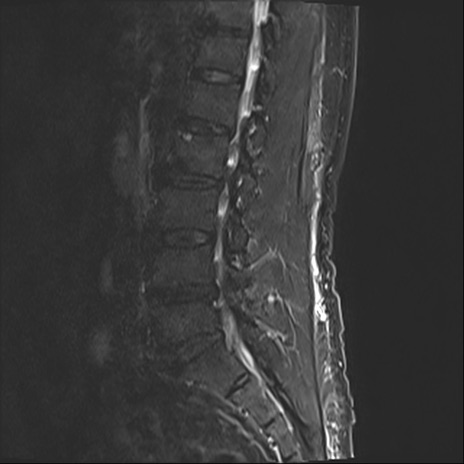

【整形】TIPS症例2 腰椎MRI STIR(矢状断像)

【症例】70歳代男性

【主訴】左下肢痛

【現病歴】2週間前くらいから腰痛、左下肢痛あり。左臀部から大腿、下腿外側のしびれが常時ある。歩行とともに同部位の痛みあり。

【身体所見】Lasegue70-/60+、Bragard-/±、PTR ±/±、ATR -/-、IP 5/5、TA 5/4、TS 5/5、EHL 右第1足趾なし/3、FHL 5/5、hypersthesia(-)、足背動脈触知良好

異常所見と診断は?